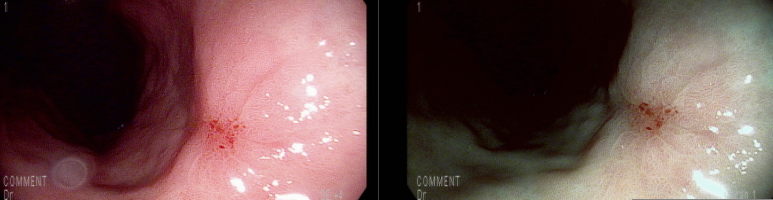

상기 환자 PPI 궤양약 2개월 복용 후 추적 검사

아물어서 궤양 흔적(S2)의 소견

육안적으로 양성 소견이지만 악성을 배제하기 위한 조직검사 재검